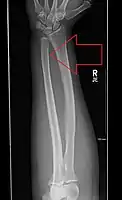

| Midshaft fracture of the radius and ulna | |

Front view of displaced fractured radius and ulna at wrist

Side view of displaced fractured radius and ulna at wrist